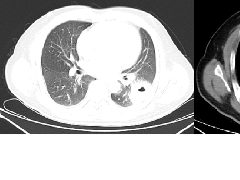

迅速增大的肺部结节,首先考虑良性,确诊需要肺穿  肺隔离症:易误诊为肺癌的占位性病变,肺穿刺禁忌!

肺隔离症:易误诊为肺癌的占位性病变,肺穿刺禁忌!  肺段与肺内管道应用解剖

肺段与肺内管道应用解剖  肺转移瘤的十种不典型CT表现